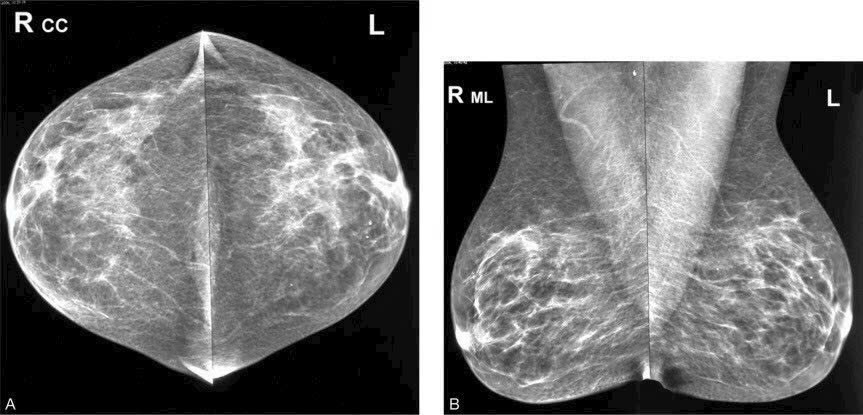

Khi chỉ chụp một bên vú, kết quả thu được sẽ chỉ phản ánh tình trạng của bên vú đó, không thể phát hiện các tổn thương có thể tồn tại ở bên vú còn lại. Điều này đặc biệt nguy hiểm đối với những tổn thương bất đối xứng, là dạng tổn thương chỉ có thể được phát hiện khi chụp X-quang cả hai bên. Nếu bỏ qua việc chụp bên vú còn lại, có thể bỏ sót tổn thương nguy hiểm.

Tổn Thương Nghi Ngờ Nếu bạn phát hiện có tổn thương qua siêu âm và bên vú còn lại không có dấu hiệu nghi ngờ, thì việc chụp X-quang cả hai bên là rất quan trọng. Siêu âm chỉ là phương pháp hỗ trợ, không thể thay thế cho việc chụp X-quang, vì X-quang có thể phát hiện những bất thường mà siêu âm không nhận ra, giúp tăng khả năng phát hiện các bệnh lý tuyến vú.